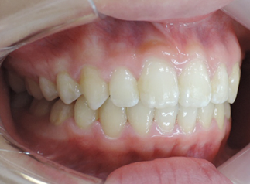

初診時

終了時

術後3年後

術後4年後

当矯正歯科医院では非抜歯で治療をしています。

治療後の後戻りが矯正では問題となりますが歯を抜かないで治療しているため、後戻りも最小限で済みます。